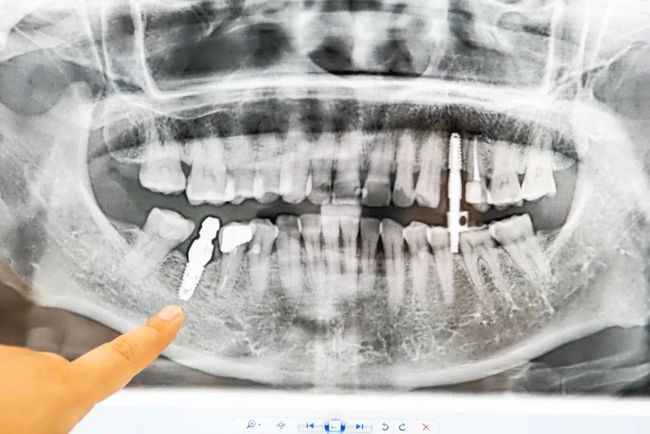

单牙缺失

种植后

多颗缺失

前后对比图

进口优质种牙材料

而海德堡口腔选用的材料是

德国进口纯钛人工牙根

使用年限至少能达10年以上

种植牙不需要损伤两侧的邻牙,

不仅坚固耐用,还可以防止牙骨萎缩。